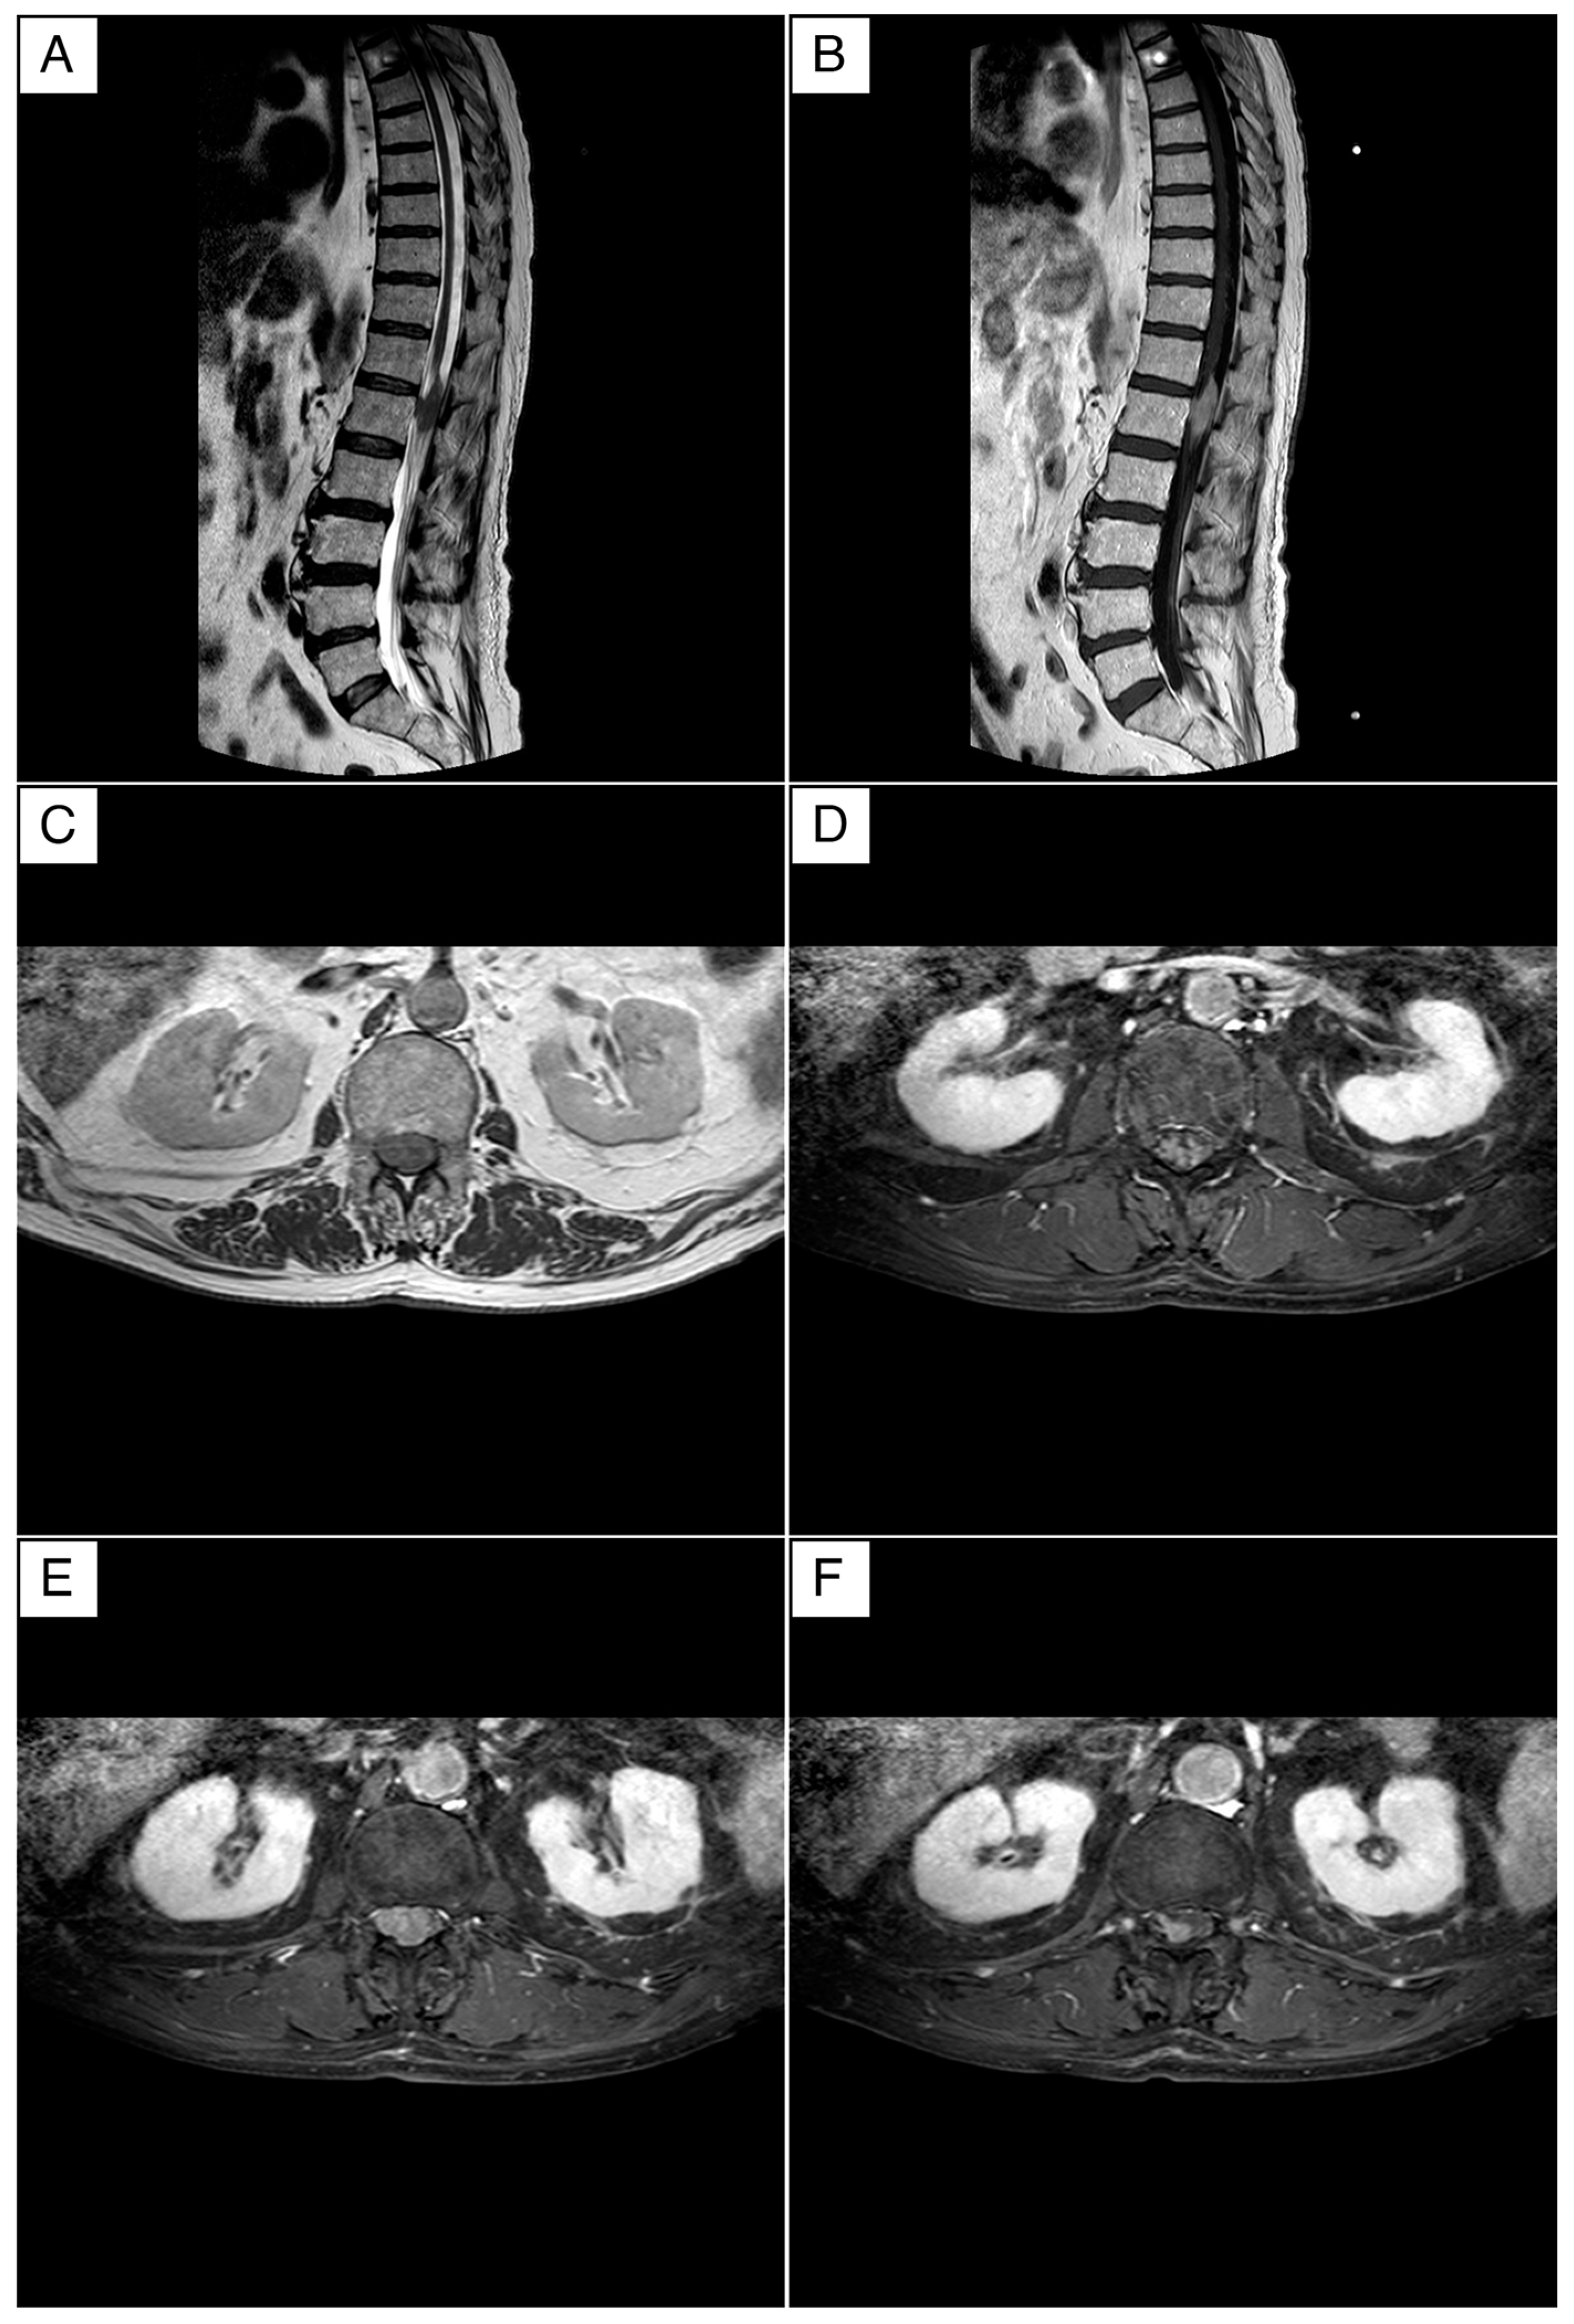

Magnetic resonance imaging (MRI) of the thoracic–lumbar–sacral spine was performed using conventional biplanar sequences, both with and without fat saturation, before and after the administration of a gadolinium-based contrast agent (ProHance® Bracco Diagnostics Inc., Milan, Italy). The imaging focused on the vertebral canal, particularly at the D12 and L1 levels.

The MRI identified a large intraspinal, extra-axial lesion at the D12/L1 level, measuring approximately 36 mm in longitudinal diameter (Figure 1A,B). On T1-weighted sequences, the lesion appeared hyperintense, while on T2-weighted sequences, it was hypointense. Post-contrast images showed homogeneous signal enhancement, confirming its solid nature and measuring about 36 mm. These imaging characteristics suggested the lesion was an extra-axial meningioma, likely with a short right anterolateral dural tail implant, indicative of a dural tail sign.

The lesion was compressing the spinal cord without infiltrating the cauda or the dura mater, as shown in Figure 1C–F. Despite the compression, there was no evidence of infiltration into the surrounding structures. The radiology department’s head, with over 25 years of experience, reviewed the MRI findings and confirmed the initial diagnosis of an intraspinal intradural meningioma.

Figure 1. Magnetic resonance imaging (MRI) of the dorso–lumbar spine. (A) The T2-weighted sagittal MRI demonstrates an extra-axial lesion exhibiting a hypointense signal. (B) The T1-weighted sagittal MRI demonstrates a lesion exhibiting a hyperintense signal. (C) The T2-weighted axial MRI demonstrates a structure that compresses but appears to not infiltrate the cauda. (DF) Gadolinium-enhanced T1-weighted axial MRI shows an extra-axial lesion with homogeneous signal enhancement. This lesion appears to be of extra axial origin, and the characteristics of signal and enhancement can be attributed in the initial hypothesis to a meningioma with a probable short right anterolateral implant in accordance with an image attributed to a dural tail.